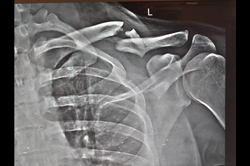

Clavicle